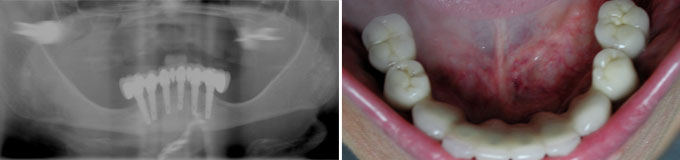

J’ai un appareil amovible haut et bas, je ne supporte plus le bas et le haut il bouge trop.

Solution : on supprime l’appareil du bas en mettant des implants qui servent à fixer un bridge fixe et en haut on place deux implants pour faire mieux tenir l’appareil mobile.

Dans ce cas, en bas 6 implants servent à réaliser un bridge fixe de 12 dents et en haut deux implants servent à stabiliser un appareil amovible.